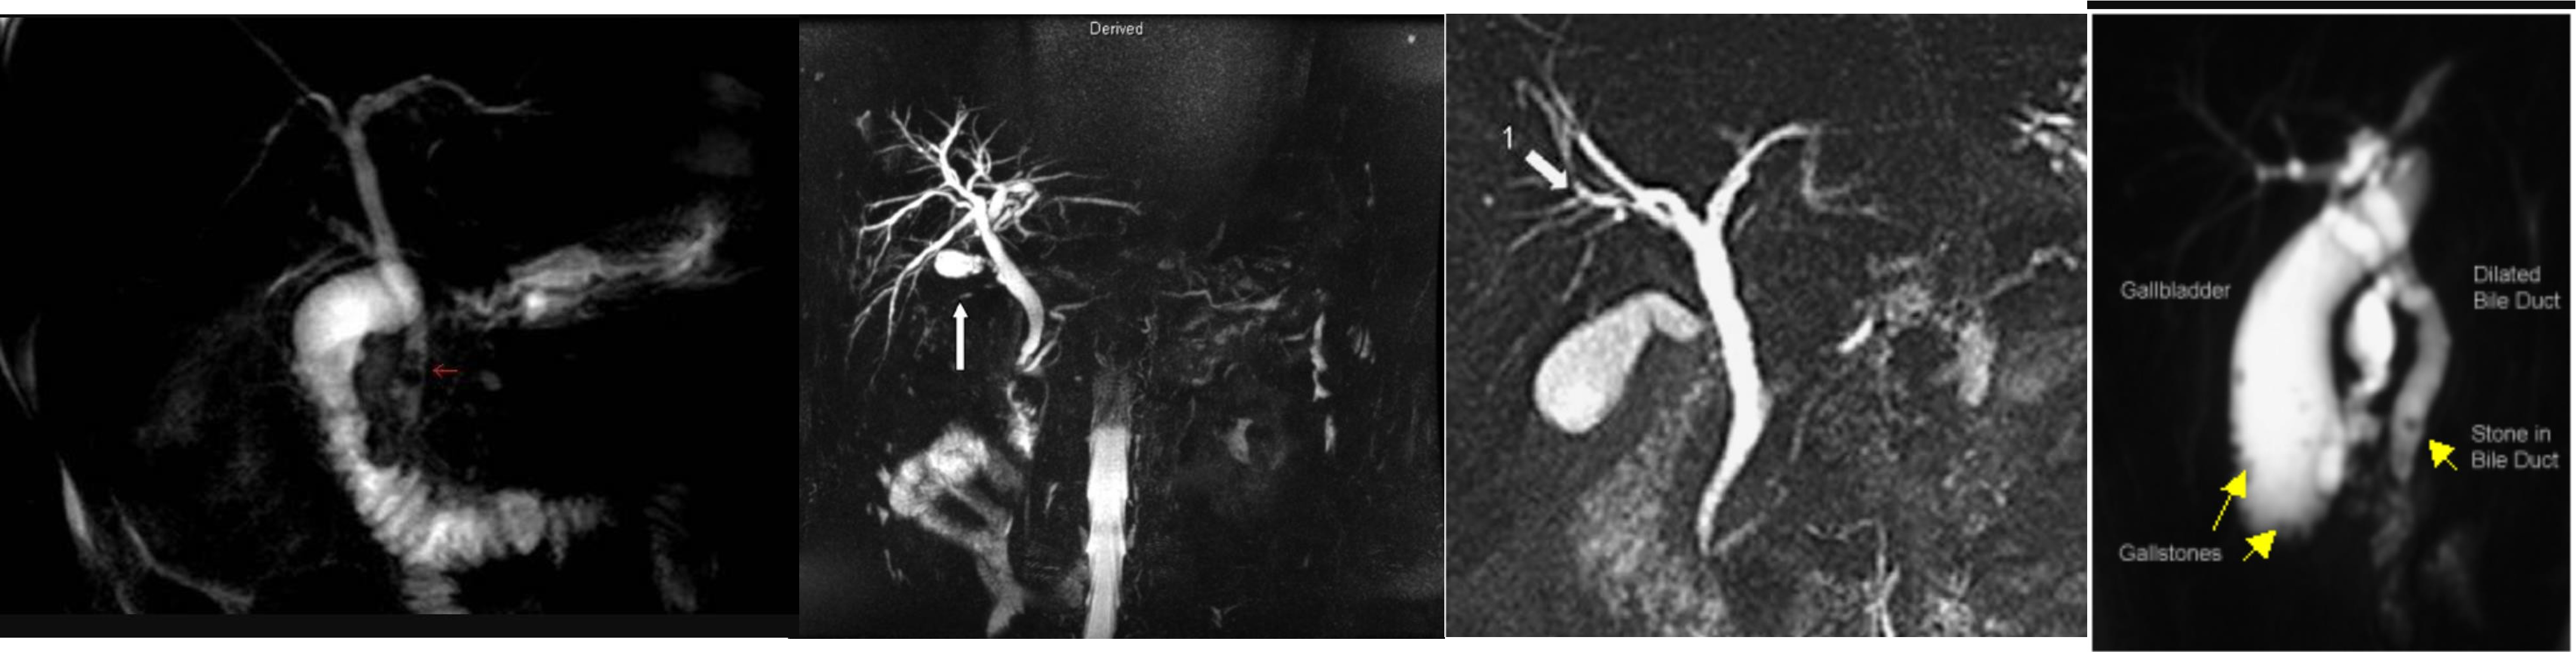

MRCP

diagnostic therapeutic anatomical

ERCP

- ERCP

- ERCP dilated (diff stone, tumour)

- dilated cbd, stone

- 3 - d. basket?